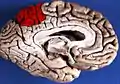

Medial surface of left cerebral hemisphere. (Precuneus visible at top left.)

In neuroanatomy, the precuneus is the portion of the superior parietal lobule on the medial surface of each brain hemisphere. It is located in front of the cuneus (the upper portion of the occipital lobe). The precuneus is bounded in front by the marginal branch of the cingulate sulcus, at the rear by the parieto-occipital sulcus, and underneath by the subparietal sulcus. It is involved with episodic memory, visuospatial processing, reflections upon self, and aspects of consciousness.

The precuneus is located on the inside between the two cerebral hemispheres in the rear region between the somatosensory cortex and forward of the cuneus (which contains the visual cortex). It is above the posterior cingulate. Following Korbinian Brodmann it has traditionally been considered a homogeneous structure and with limited distinction between it and the neighboring posterior cingulate area. Brodmann mapped it as the medial continuation of lateral parietal area 7.